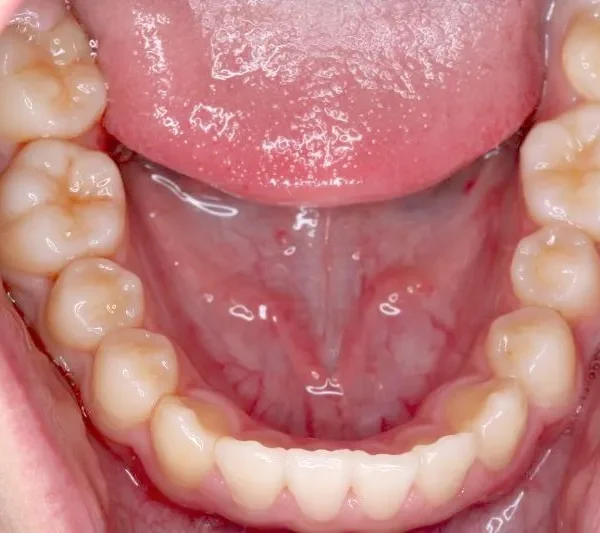

まずは装置で歯のアーチを広げ、歯の生えるスペースを作り、中に入ってる上の前歯を外に押し出して正常な噛み合わせにします。

治療回数44回、5年5ヶ月の治療期間で矯正治療を終了しました。

主訴が改善され、ご満足頂きました。

治療終了後